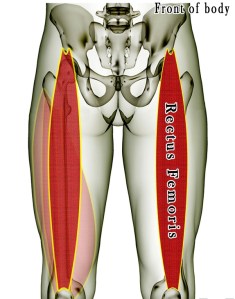

Rectus Femoris

The rectus femoris muscle is one of the four quadriceps muscles that sits in the middle of the front of the thigh.

The rectus femoris attaches from the pelvis to just below the knee (on the patellar tendon.) It is responsible for knee extension and hip flexion.

The other muscles of the quadriceps include the vastus medialis, the vastus intermedius and the vastus lateralis.

It is one of the muscles that make up the hip flexors; a group of muscles that bring the legs and trunk together in a flexion movement.

| ORIGIN Straight head: anterior inferior iliac spine. Reflected head: ilium above acetabulum |

| INSERTION Quadriceps tendon to patella , via ligamentum patellae into tubercle of tibia |